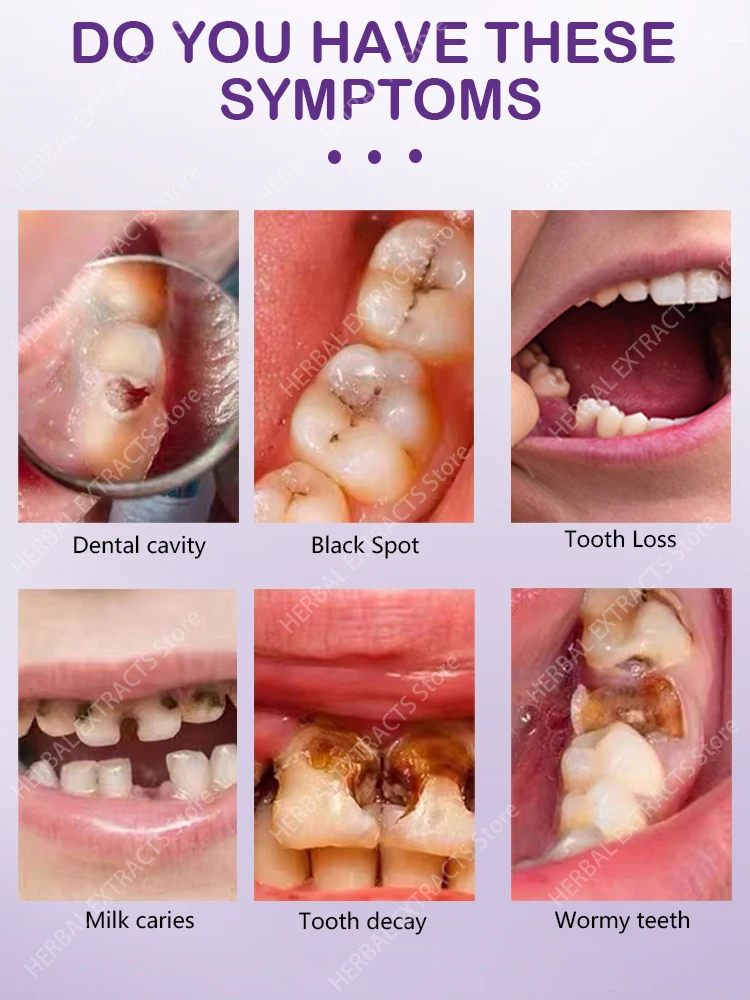

How can you tell if your headache is indeed linked to a decayed tooth? Look out for these accompanying symptoms:

- A persistent, throbbing toothache that might worsen when you chew or apply pressure.

- Increased sensitivity to hot or cold foods and drinks.

- Swelling or tenderness around the affected tooth or in your jaw.

- A bad taste in your mouth, which could indicate an infection.

- Pain that radiates from your tooth to your ear, temple, or neck.

- Headaches that seem to occur on the same side as the painful tooth.

If you're experiencing a combination of these symptoms, it's a strong indicator that your decayed tooth could be the root cause of your headache.